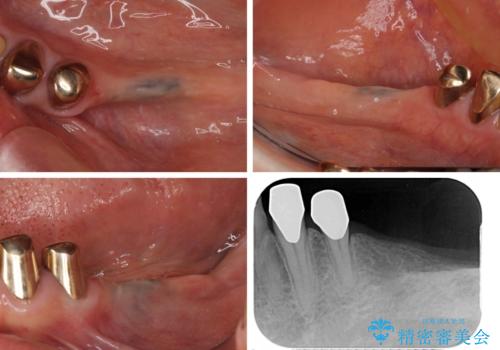

- 義歯を使いたくないものの、骨の幅が狭くインプラント治療を断られているとのことで来院された患者様です。

レントゲンやCTより、骨の高さと幅が不足しており、骨を増やす必要のある状態でした。

しかしながら、全身疾患により骨造成術の予後に不安があったため、デンサーバー(Densah ® Bur)という骨幅を増大することが可能なドリルを用いてインプラントを埋入することとしました。

入れ歯の支台となっていたコーヌスのゴールドも除去し、インプラント部と合わせてオールセラミッククラウンにて補綴治療を行うこととしました。